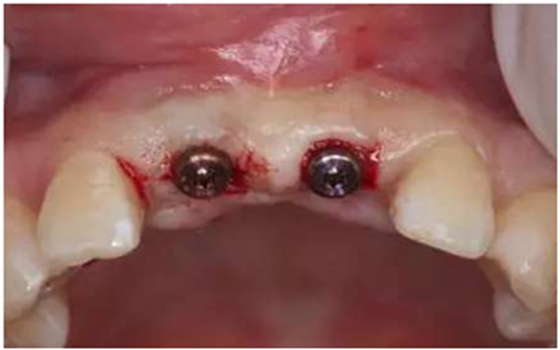

種植二期手術(shù):

連接愈合基臺(tái)

愈合基臺(tái)連接2周后